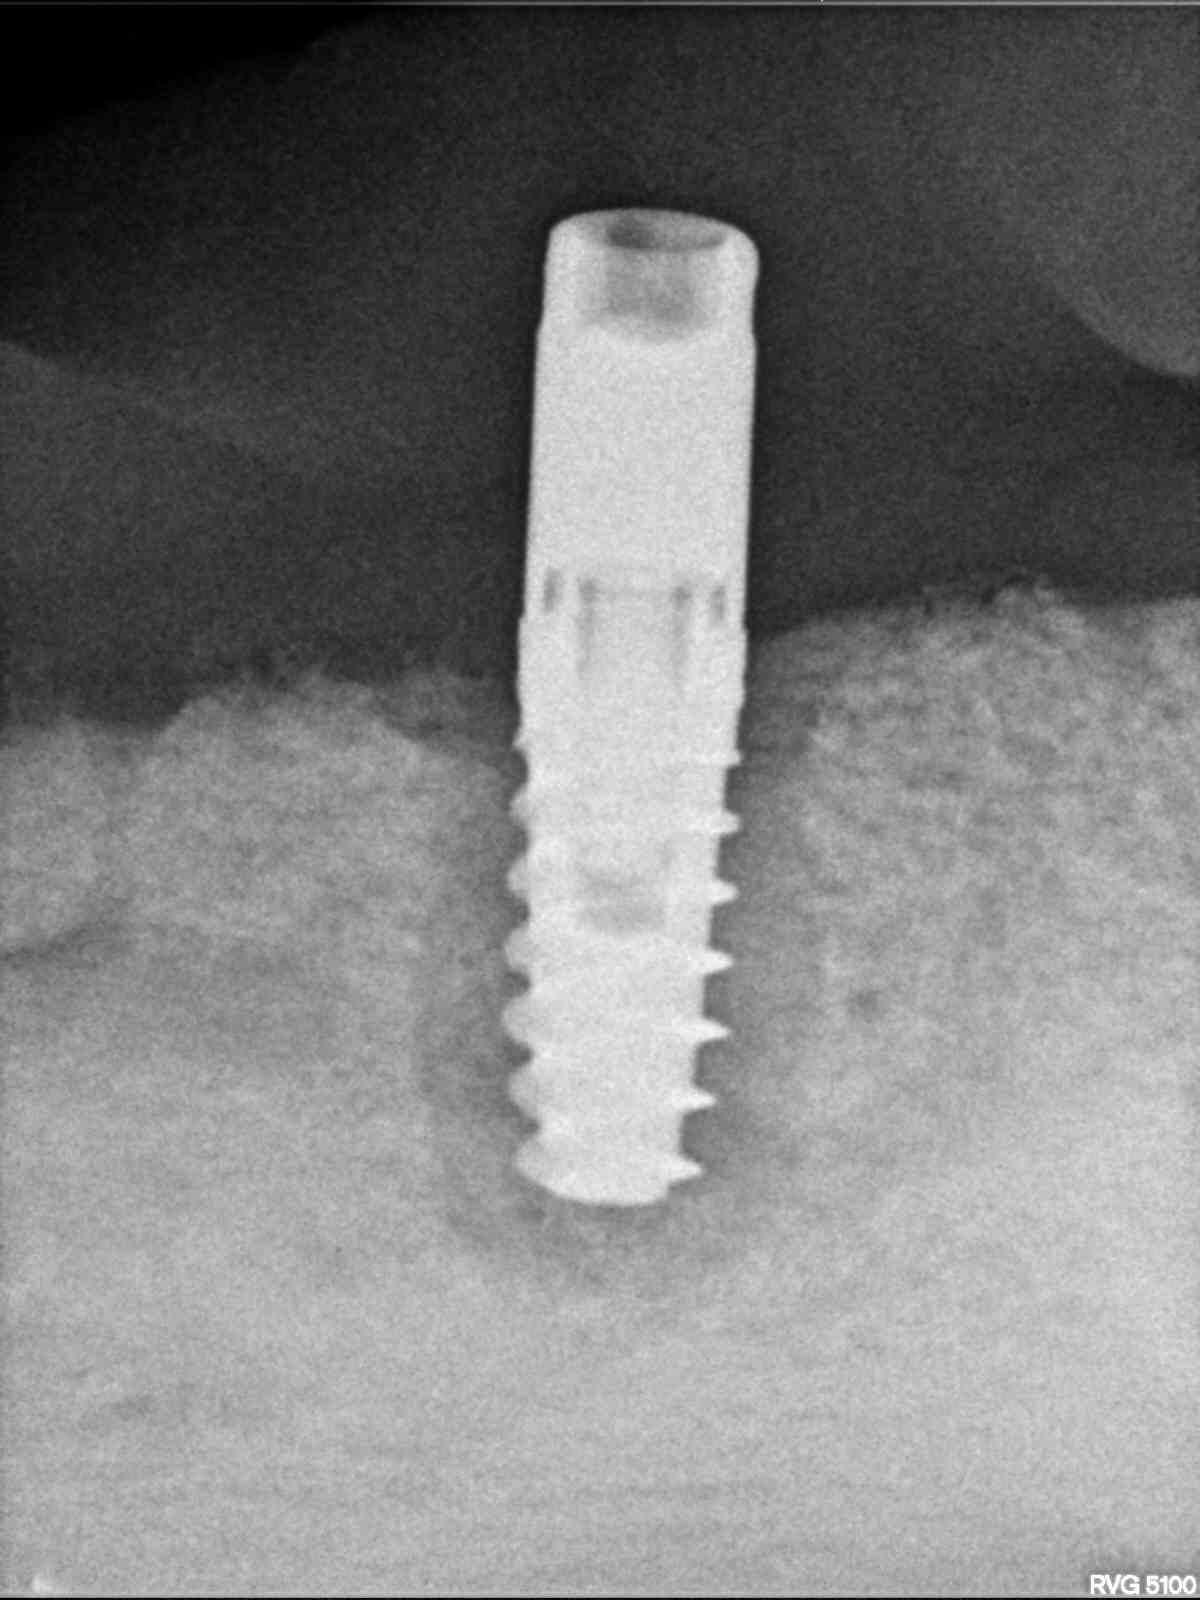

Me ayudan para saber que implante y medida es? Gracias

Buenos días. Me pongo en contacto con vosotros para que me ayudéis con este caso. Este implante es para extracción, pero tiene al lado uno igual al que voy a [...]

Le han puesto dos, en 47 y 48 pero el 48 no lo voy a rehabilitar. les agradecería conocer especificaciones del implante del 47 para poder rehabilitarlo gracias. son implantes [...]